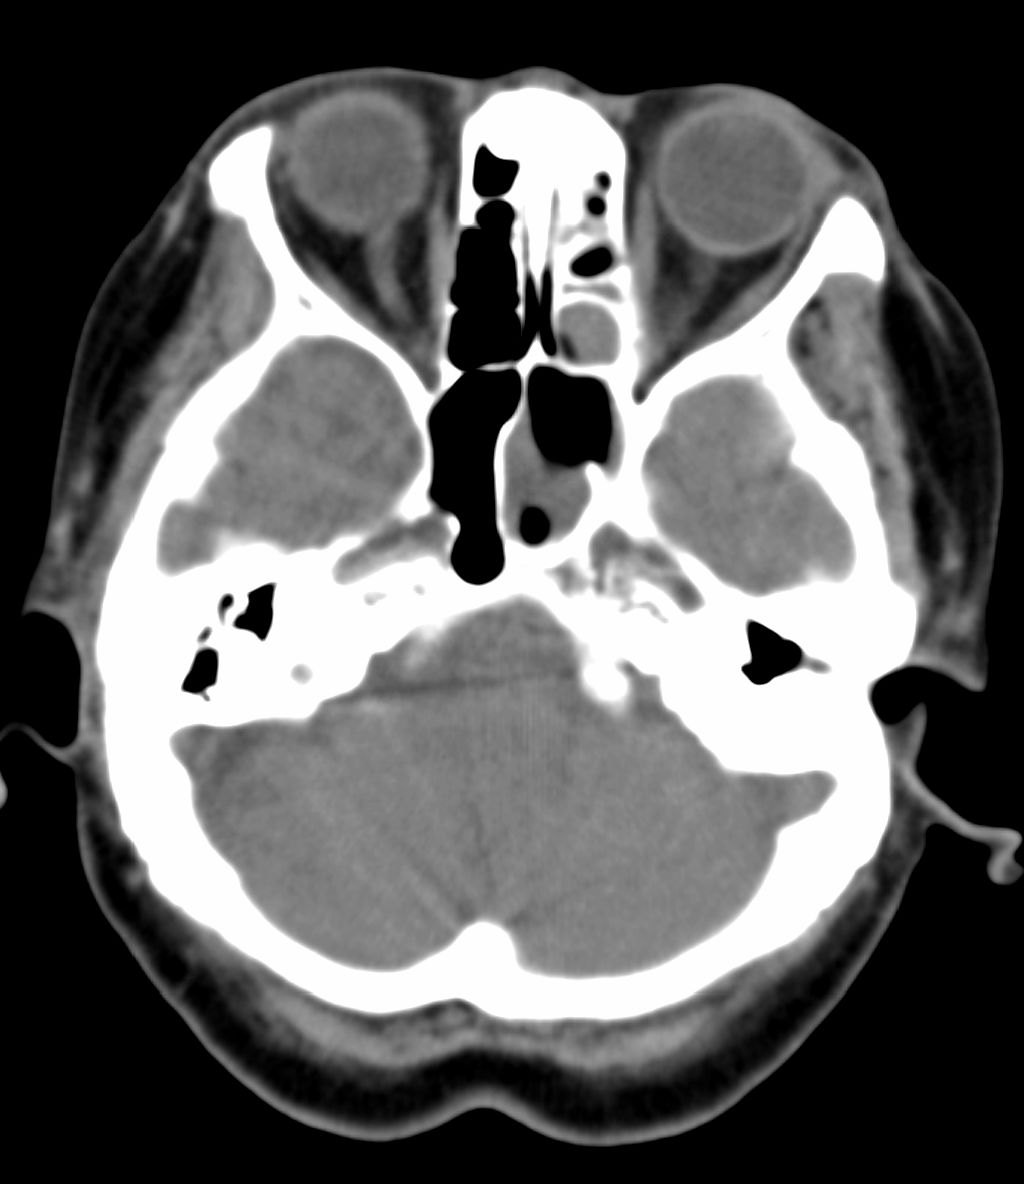

女,69岁。鼻出血2月多。(会诊病史就这样简单)鼻副窦ct检查如下:

左侧鼻腔及上颌窦见软组织块影,左侧上颌窦腔扩大,骨质吸收,右侧上颌窦见半圆形软组织密度影,鼻中隔向右侧弯曲,左侧鼻和鼻窦内翻型乳头状瘤可能性大,建议增强。

左侧上颌窦及鼻腔内见软组织密度影,其内密度不均匀,见斑片状高密度影,右侧上颌窦腔明显扩大,窦壁吸收变薄,鼻中隔右偏,右侧上颌窦见一半圆形软组织密度影,边界清楚,其内密度均匀。诊断,1、左侧鼻腔及上颌窦内翻乳头状瘤可能性大,上颌窦癌,息肉及霉菌性上颌窦炎待除外。2、右侧上颌窦粘膜下囊肿。

窦腔密度不均匀增高,无明显钙化征象,后外侧及内侧窦壁膨胀明显,局部破坏消失,筛窦受累及,但双侧对比发现左侧窦壁骨质有硬化增白现象,这可能是支持左侧霉菌性上颌窦炎的主要依据点。